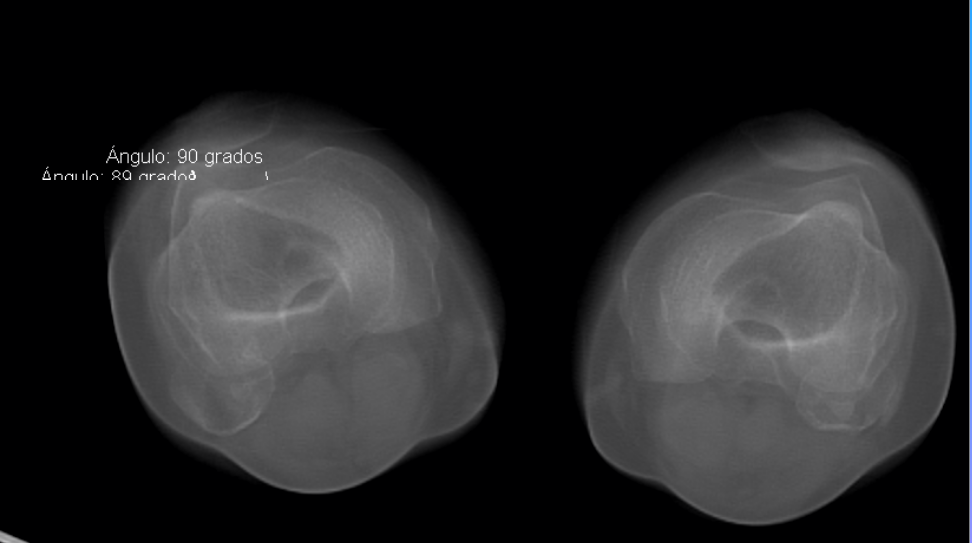

Screenshots

Before before After after